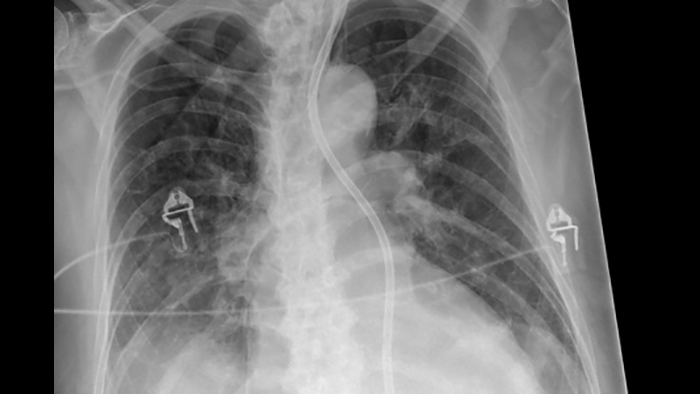

SkyFlow Plus image processing

When doing DR exams without a grid, Philips SkyFlow Plus produces images with grid-like contrast. It reduces the effect of scattered radiation for non-grid bedside chest exams. SkyFlow Plus is the industry’s first scatter correction algorithm for portable X-rays. It delivers contrast enhancement based on the amount of scatter for the individual patient.